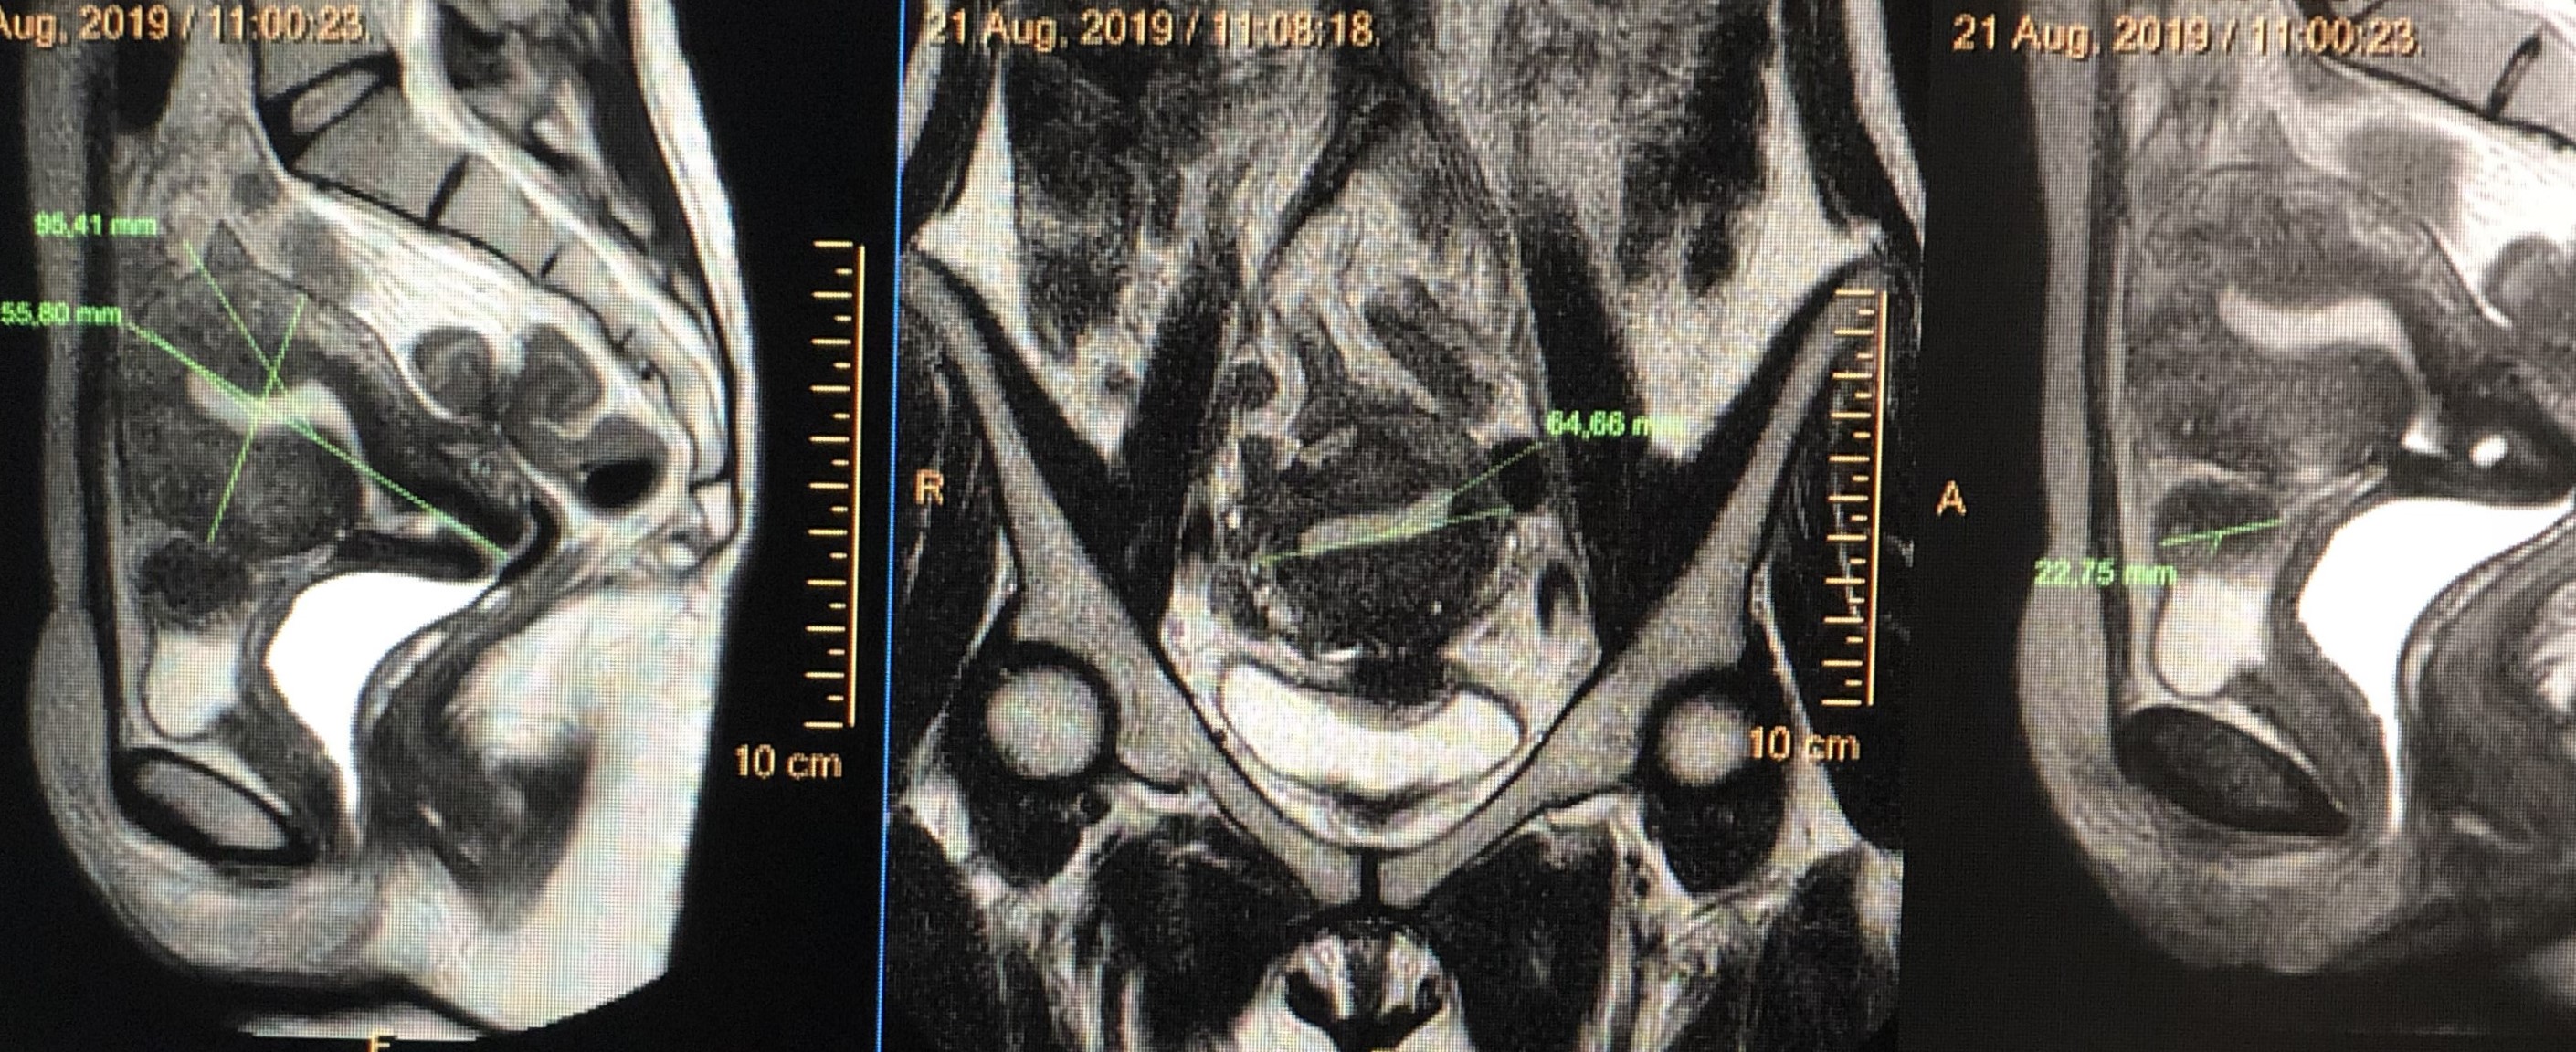

Kyste ovarien hémorragique et multiloculé

Kyste ovarien simple

Endométriose vésicale et profonde